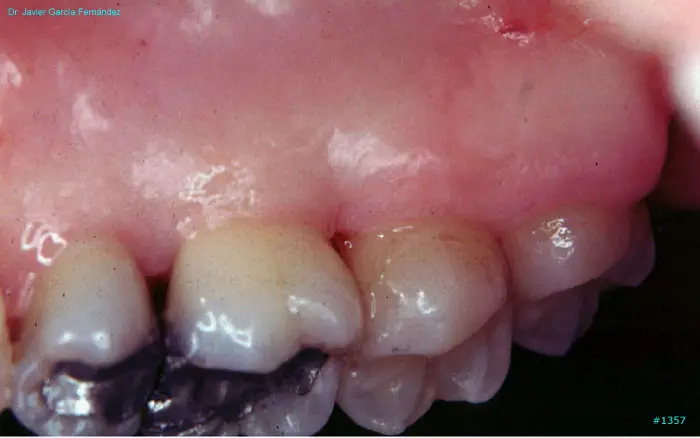

Atlas of Surgical Techniques in Periodontics. Chapter III. Atlas de Técnicas Quirúrgicas en Periodoncia